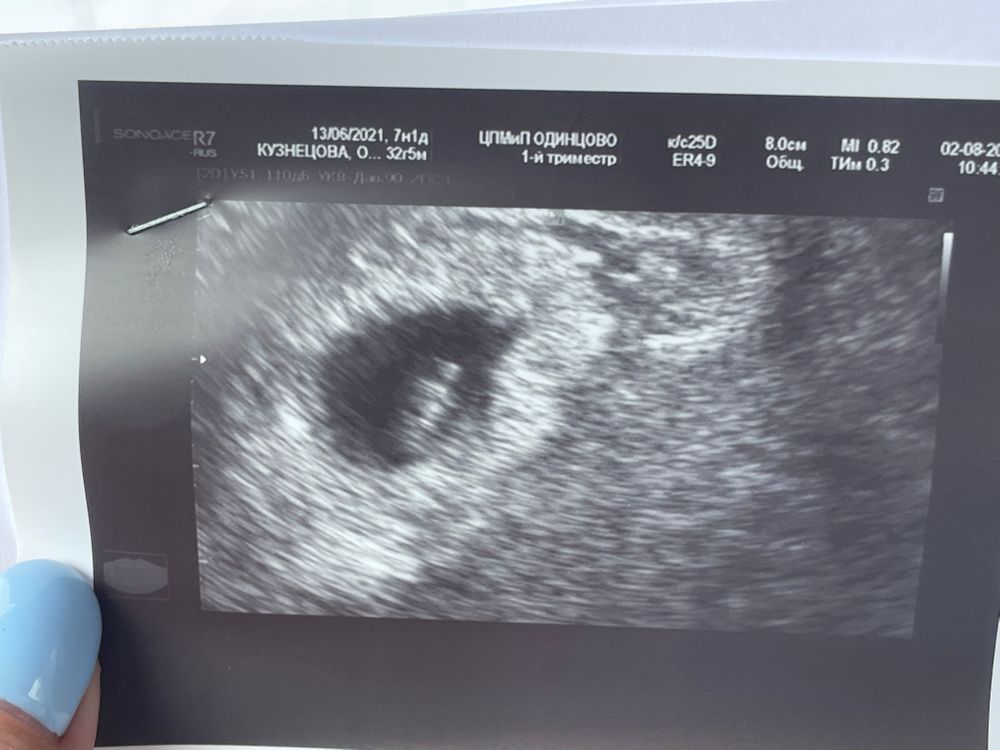

Первое узи 5ой Б

8 мм, скорее всего.

Вы ошиблись,не может быть 8 см,это тогда 80 мм и это срок на 14 недель,у вас скорее 8 мм

Марина, 8.7мм, ага)